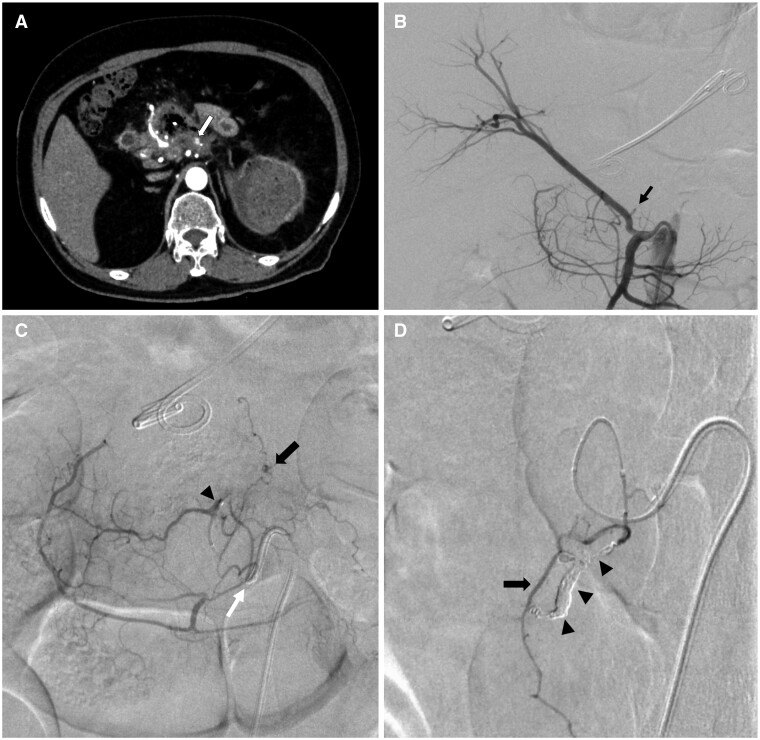

A 63-year-old man underwent transcatheter arterial embolization (TAE) using a mixture of N-butyl-2-cyanoacrylate (NBCA) and iodized oil to treat acute gastrointestinal (GI) bleeding. The procedure was initially successful; however, the patient developed ileus >1 month later and subsequently underwent several surgeries to treat the multiple metachronous ileal stenoses. The flux of a small amount of off-target glue was the primary cause of these complications. As the patient had few symptoms in the first month post-TAE, however, affirming the diagnosis took time. A detailed review of plain CT scans was a decisive factor in achieving the final diagnosis. This case demonstrates that TAE using an NBCA-iodized oil mixture effectively treats acute GI bleeding. However, a complication such as off-target embolization is likelier to occur because of a combination of certain factors such as vascular anatomy, complexity of the procedure, and NBCA dilution. Close observation using plain CT should be performed for the identification of off-target embolization occurrence even in cases of successful TAE.